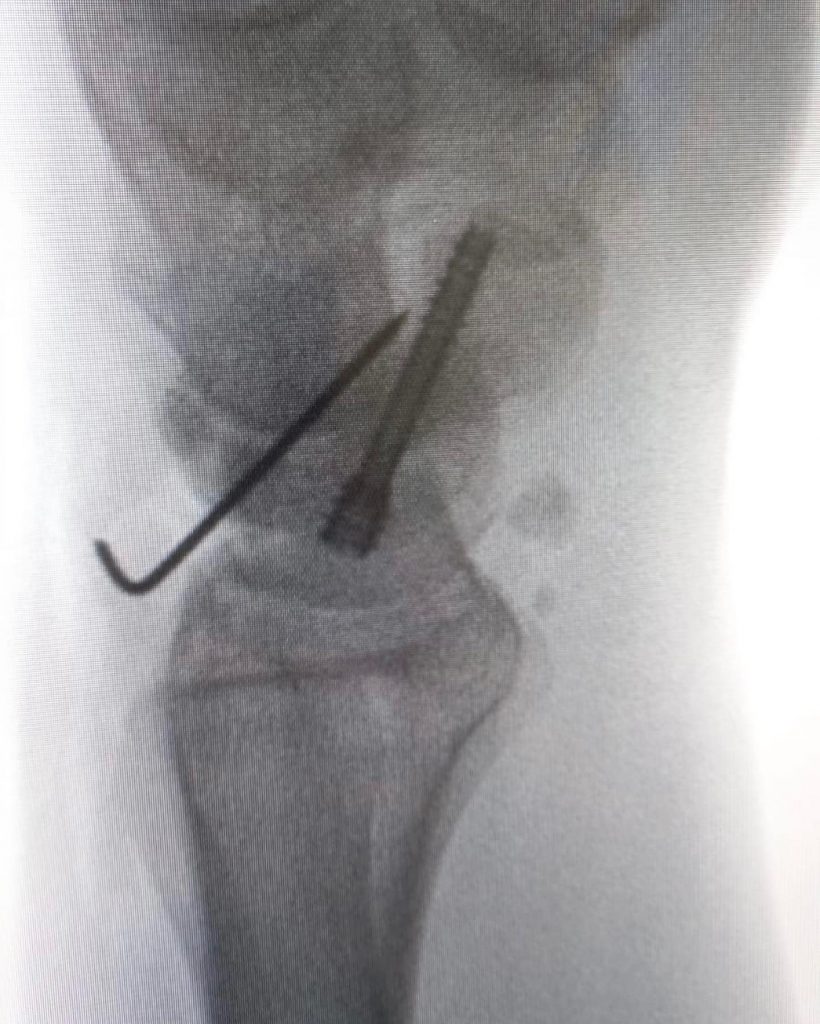

Pseudoartrose do escafóide:A pseudoartrose é uma patologia que ocorre quando não há consolidação de uma fratura após o período esperado – o osso “não colou”.

Nesses casos, é indicado intervenção cirúrgica. É uma situação comum nas fraturas do escafóide.

No caso acima, foi tratada com retalho ósseo vascularizado e fixação com parafuso de Herbert.